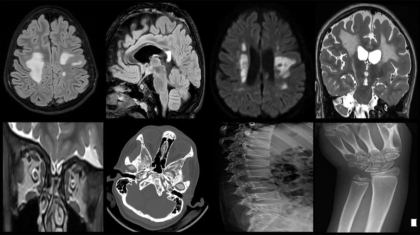

An 11-year-old female presented with complaints of progressive weakness of the left upper and lower limbs for 1 year, dysphagia for 4 months, reduced vision in the left eye for 3 months, dysarthria for 2 months, and urinary incontinence for 15 days.